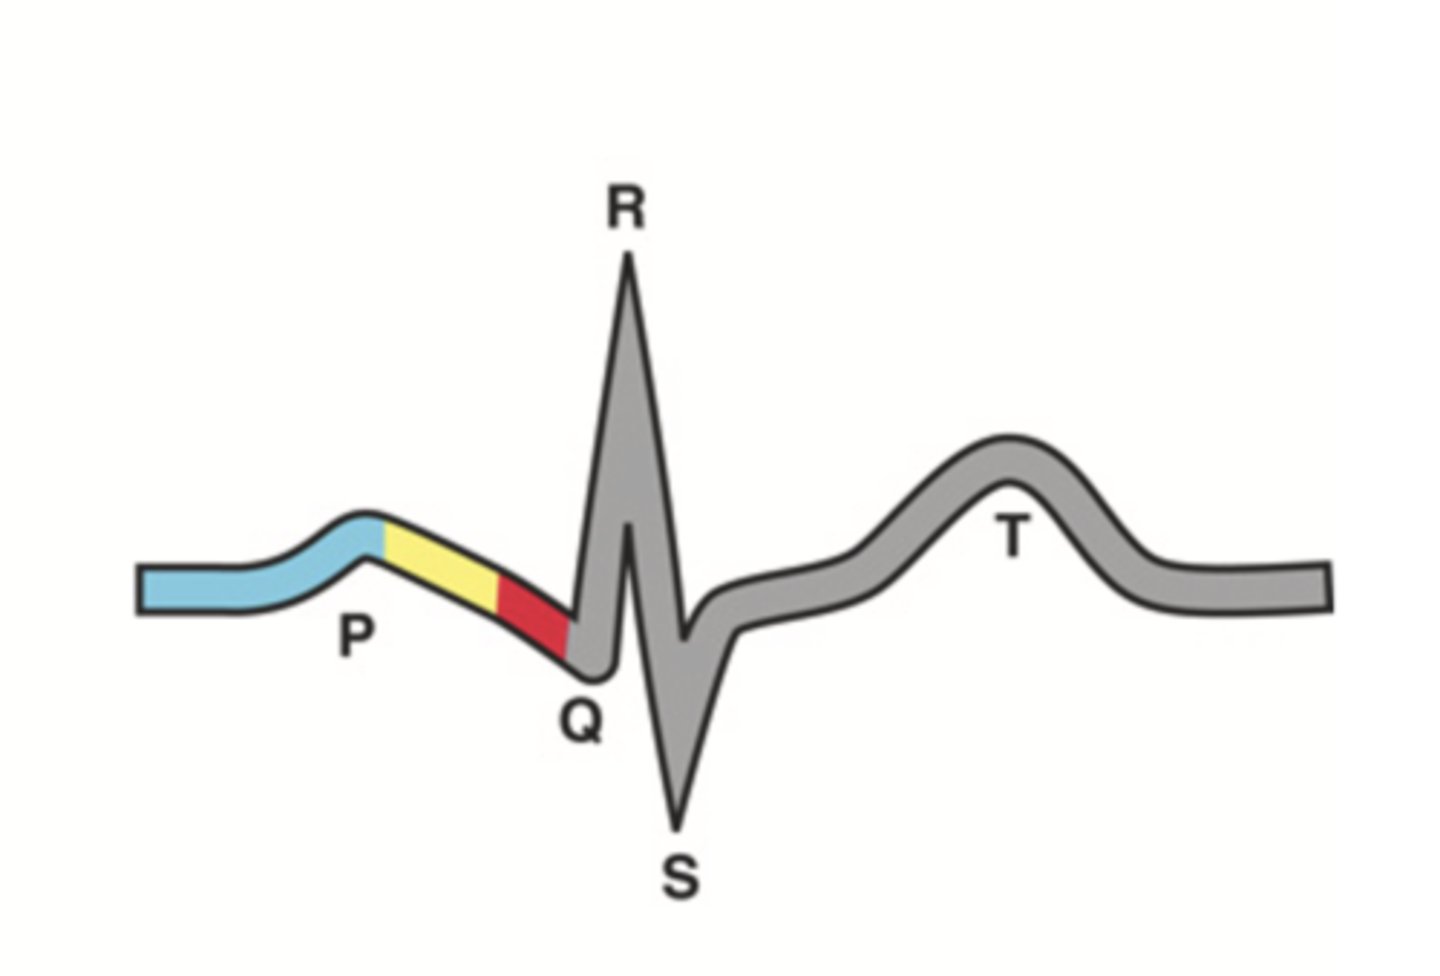

4 Parts of the Heart's Conduction System

- Sinoatrial (SA) node

- Atrioventricular (AV) node

- Bundle of His

- Purkinje fibers

Sinoatrial (SA) Node

Pacemaker of the heart conduction system, located at the right atrium (light blue)

Atrioventricular (AV) Node

The part that relays electrical impulses from atria into the bundle of his in the heart's conduction system; delayed slightly (yellow)

Bundle of His

Part of the heart's conduction system that transmits the cardiac impulse from the atrioventricular node to the purkinje fibers (red)

Purkinje Fibers

Fibers in the ventricles that transmit impulses to the right and left ventricles, causing them to contract

ECG Waves

- P wave

- P-R interval

- QRS complex

- Q-T interval

- T wave

P Wave

Atrial depolarization

P-R Interval

Atrial contraction

QRS Complex

Ventricular depolarization

Q-T Interval

Ventricular contraction

T Wave

Repolarization of ventricles